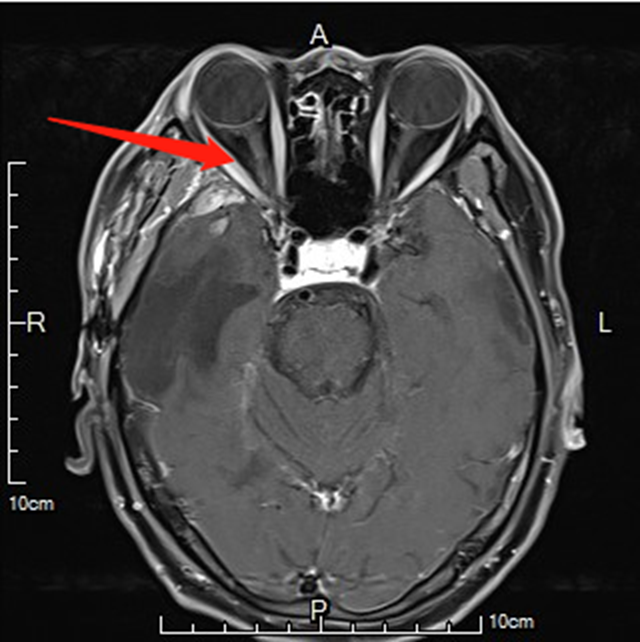

2023年5月底,胡大叔出现了右眼胀痛、视物模糊、右眼球外突的症状,便来到了西南医科大学附属中医医院就诊。医生为其做了眼眶MRI检查,结果提示右眼眶外侧壁、上壁及右侧蝶骨翼软组织有肿块的影子,结合胡大叔肺癌的病史,考虑是肿瘤复发伴眼眶颅底颅内转移。

经过对胡大叔右侧眼眶、颅底、颅内转移病灶调强放疗后,肿瘤明显缩小。又进行了几次调强放疗后,胡大叔右侧眼球肿胀消失、视力恢复正常。